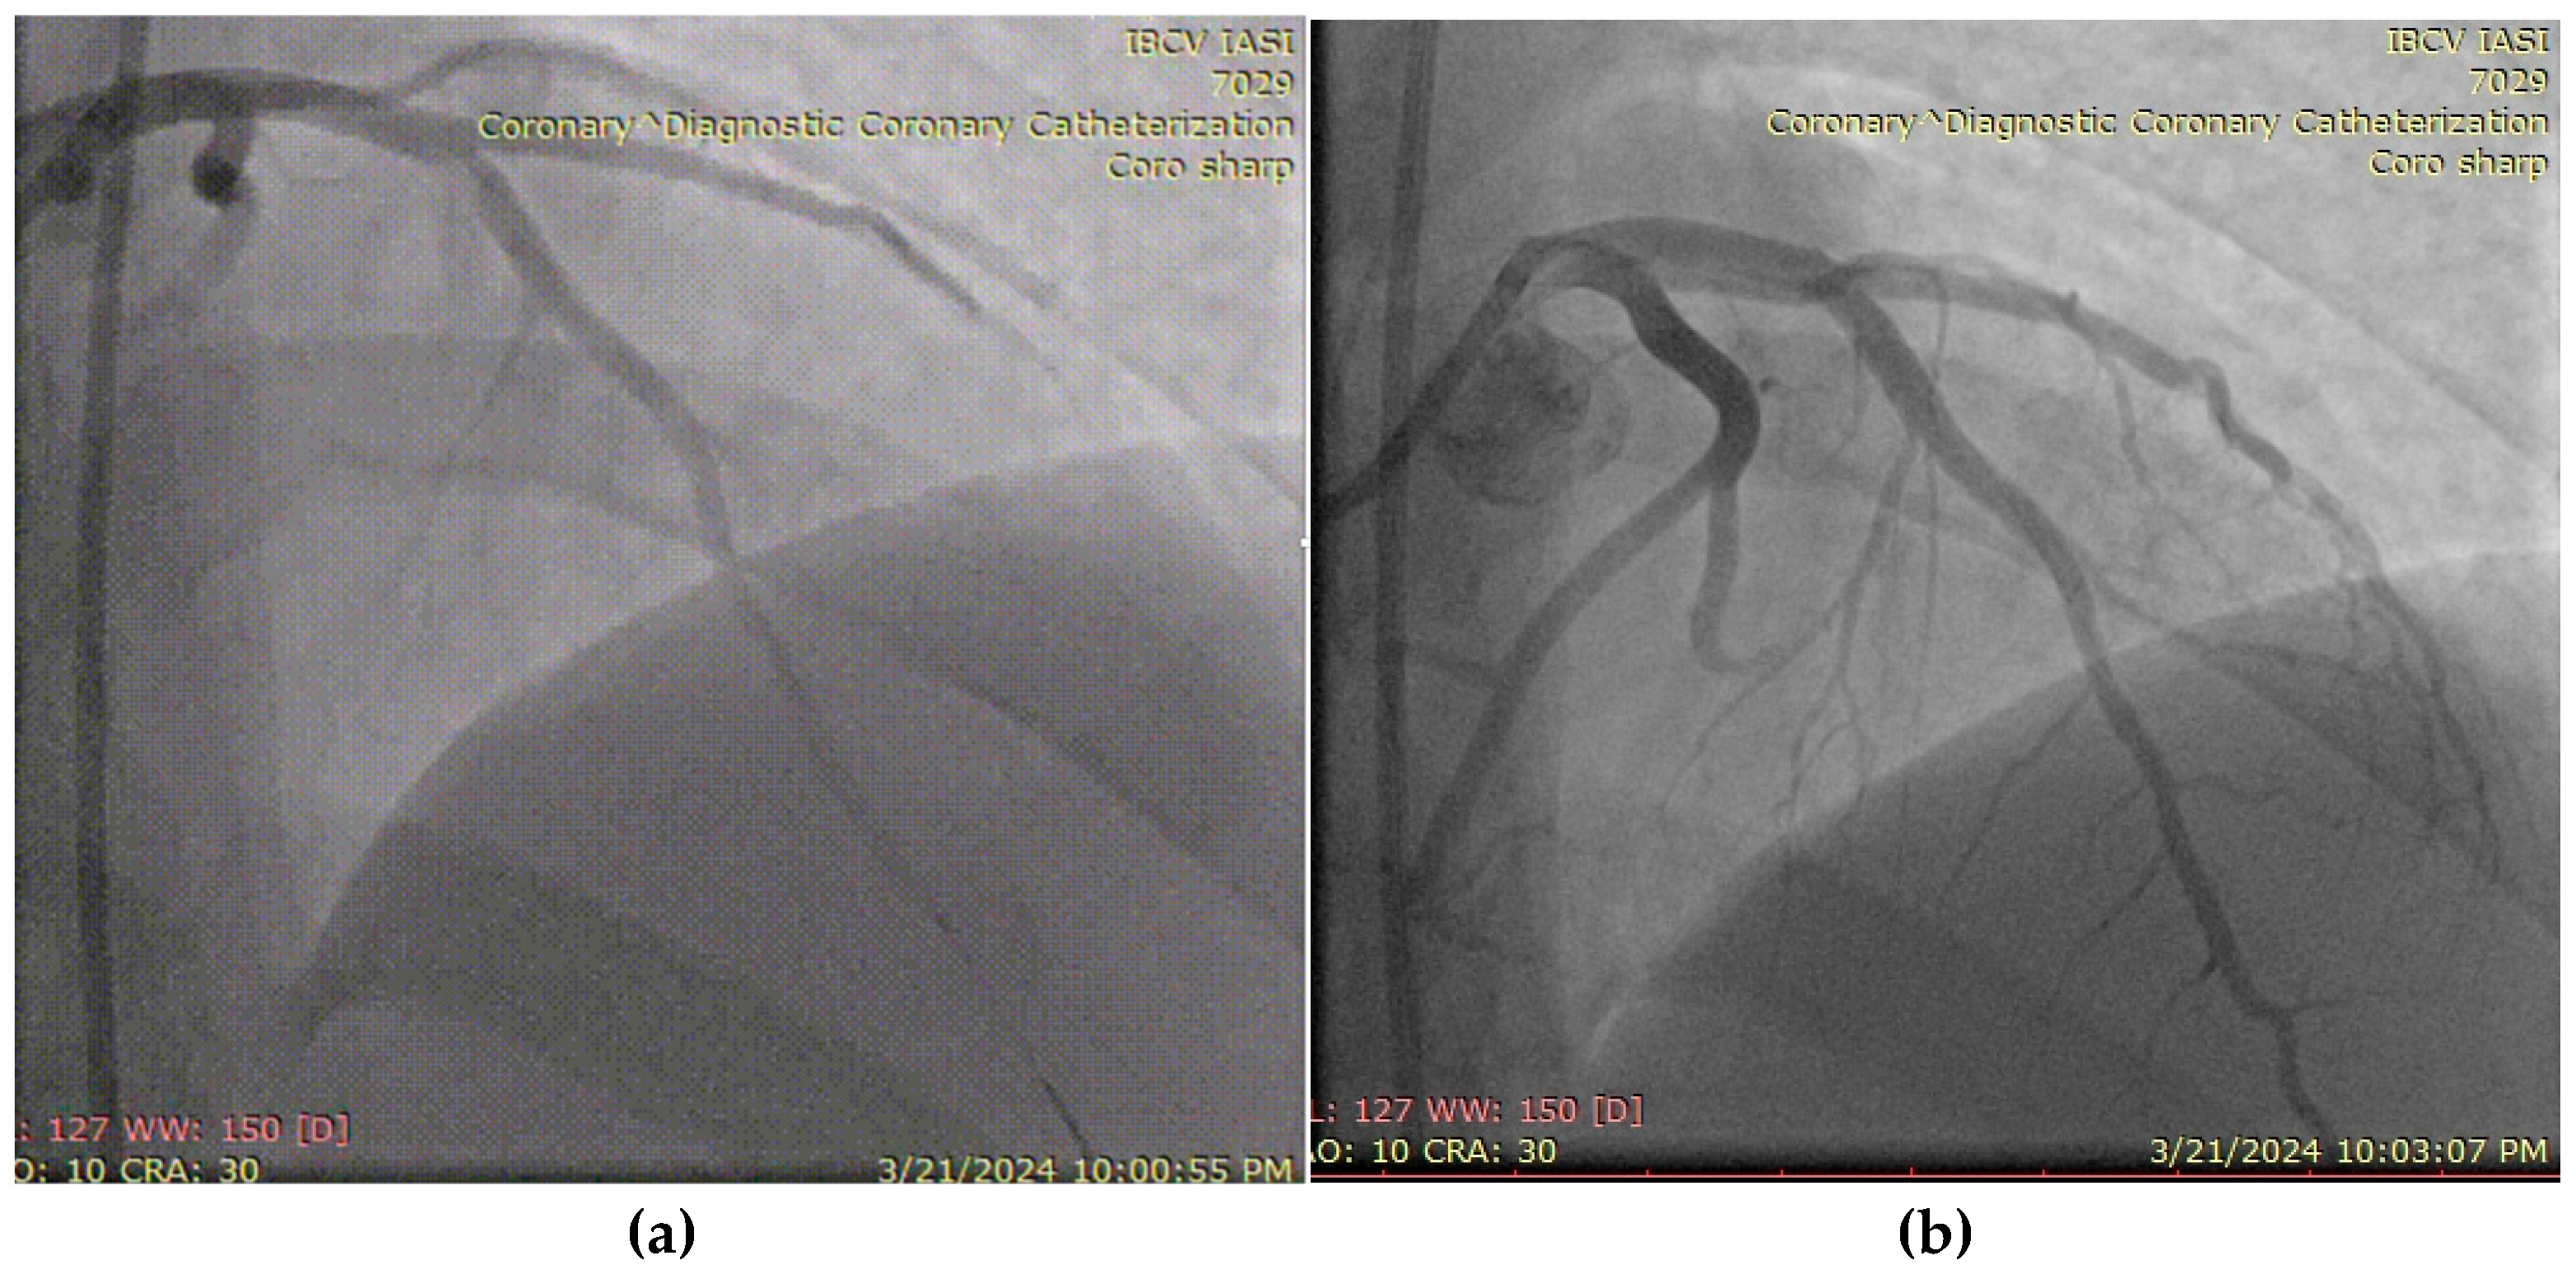

3.4. Case 4